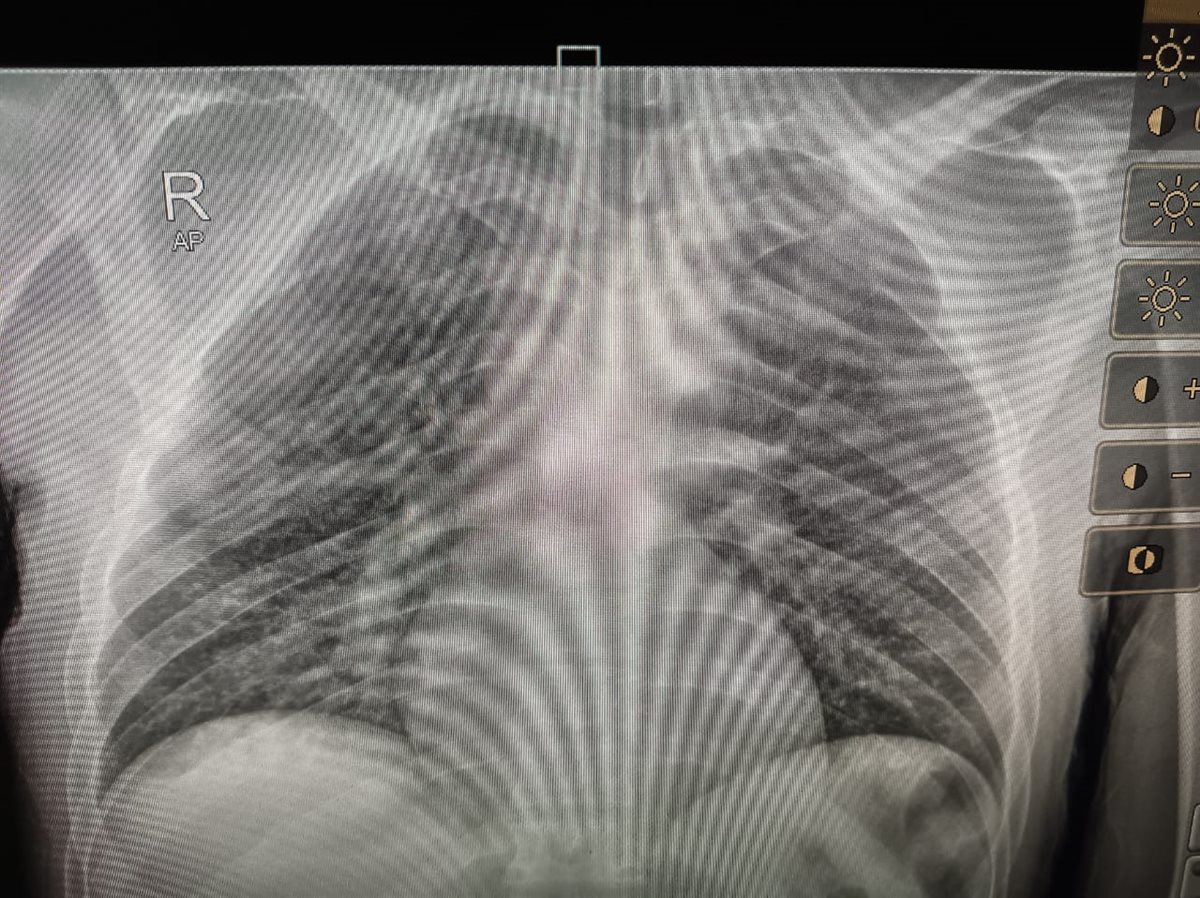

المريض بورم في المخ

استغاث شقيق مريض ورم بالمخ، من رفض مستشفى الحسين استقبال الأخير بالعناية المركزة، حيث يعاني من مضاعفات صحية شديدة من فقدان النطق، بعد 4 أشهر من إجراء عملية لإزالة الورم في المستشفى.

وأوضح مصطفى شقيق المريض في تصريحات خاصة لـ القاهرة 24: شقيقي عانى من مضاعفات صحية شديدة بعد 4 أشهر من إجراء عملية إزالة الورم بالمخ في مستشفى الحسين، وعندما ذهبنا لهم خلال هذه الأيام لعلاجه أو لتشخيصه أخبرونا أنه يحتاج لعناية مركزة وأعداد المرضى مكتملة، ولا يوجد أي طاقة استيعابية في العناية المركزة لاستقبال أي مريض، والحالة دي بتسوء مني وليس لدي أي مقدرة لدخوله عناية مركزة بمستشفى خاص.